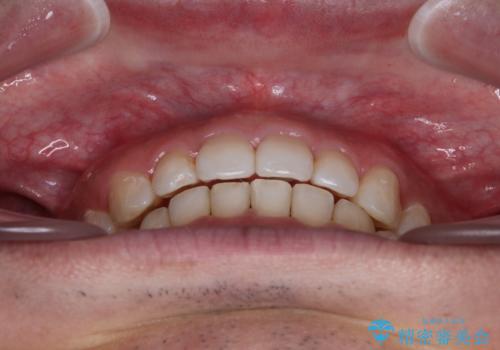

右上と左下は永久歯が欠如しており、大きさの大きく異なる乳歯が残存していたため、奥歯の咬み合わせを構築するために苦労しました。

元々隙間の空いていた上顎の正中は、後戻りのリスクが高いため、下顎前歯同様ワイヤー固定を行いました。